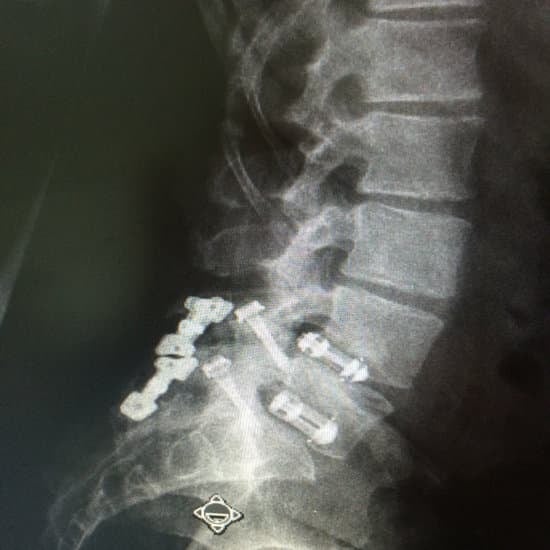

PLIF (Posterior Lumbar Interbody Fusion)는 요추(허리) 뒤쪽(후방)에서 접근해 디스크를 제거하고, 척추뼈 사이를 유합(고정)시키는 수술입니다.

디스크 제거 후 인공 뼈(케이지)를 삽입

척추 마디를 금속 나사와 봉(로드)으로 고정시간이 지나면서 뼈가 붙도록 유도 → 척추 안정화

케이지 삽입 + 뼈 이식

척추 고정 나사(Screw) 삽입